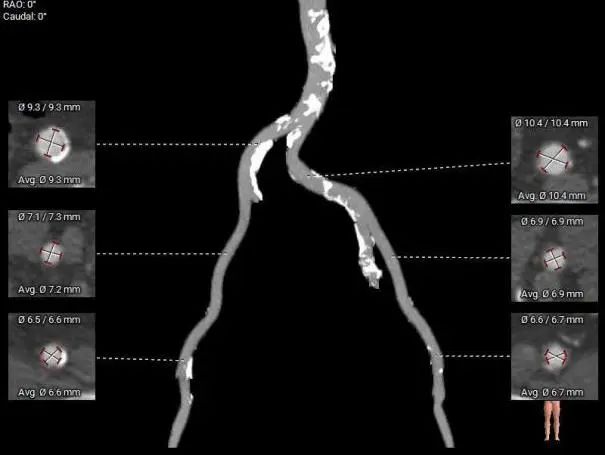

外周入路:

整体入路血管直径尚可,走行尚可腹主-髂总钙化分布较多

•-股-髂动脉走行适宜,内径可,腹主-髂总钙化分布较多,右侧股动脉穿刺点有钙化分布,股动脉分叉较高;左侧股动脉穿刺点极少钙化。